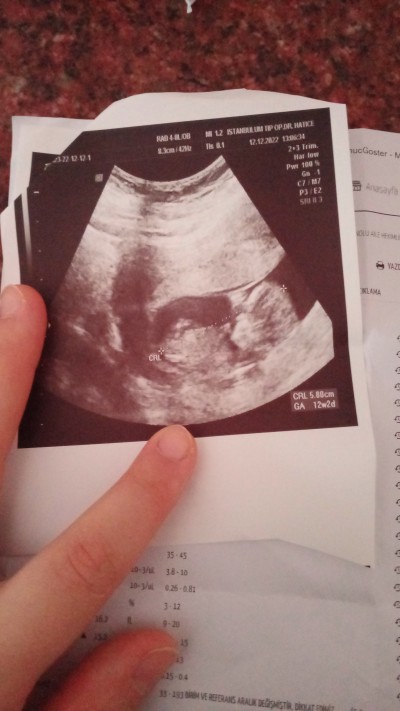

Meraba hanimlar 2 oglum var tekrar hamileyim 12+2  haftalik hamileyim kiza benziyor dedi ama emin olamadim ultrason reskinr gore anlayan varmi

Gebelik haftası 12+2